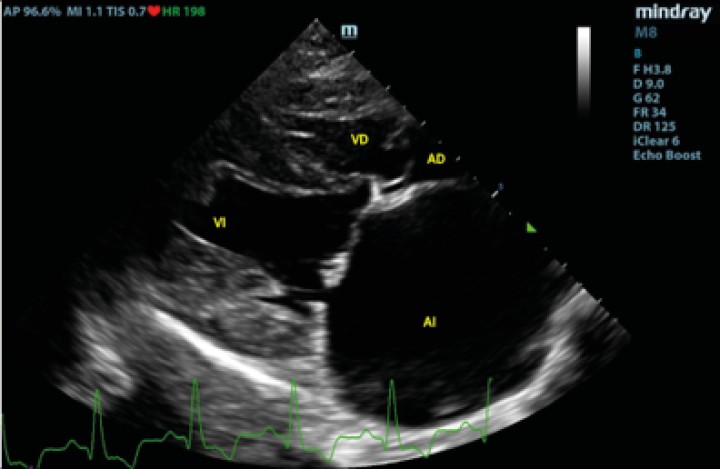

Posteriormente se evaluó al paciente mediante un examen TFAST, detectando derrame pericárdico y disminución del tamaño del AI (Fig. 4), como hallazgos diferentes a los observados en el examen realizado previo a la radiografía. La rápida respuesta por parte del equipo veterinario implicó que en este primer examen ecográfico tras el desvanecimiento del paciente no se había producido la formación del coágulo para taponar la fisura de la pared, observando flujo desde el AI hacia el saco pericárdico. Se realizaron exámenes TFAST seriados para evaluar la necesidad de realizar una pericardiocentesis al paciente durante la hora siguiente al episodio. En los exámenes seriados realizados no se observaron signos ecocardiográficos de taponamiento cardíaco, por lo que se decidió no realizar un vaciado del contenido pericárdico mediante pericardiocentesis[ Rush JE: Cardiac emergencies. En Rozanski EA and Rush JE (ed): Small Animal Emergency and Critical Care Medicine: A Colour Handbook, London, Manson Publishing, 2007; 52-56 , Kirby R: Cardiovascular case 79. En Kirby R (ed): Self-assessment color review of small animal emergency & critical care medicine, London, Veterinary Press, 1998; 67-71. ] y se optó por un tratamiento de soporte basado en oxigenoterapia y fluidoterapia, buscando mantener un correcto gasto cardíaco sin aumentar en exceso la presión sistólica del paciente, lo que podría producir un aumento del sangrado a través del defecto de la pared atrial, así como una dosis única de pimobendán (Vetmedin, Boehringer Ingelheim, Rhein) por vía intravenosa a 0,15 mg/kg. A los 15 minutos tras el episodio de desvanecimiento, se observó la presencia de una estructura hiperecoica en la pared del AI en el examen ecográfico, compatible con la formación de un coágulo (Fig. 5).

<p>Examen TFAST tras la rotura del atrio izquierdo donde podemos observar un corte transversal del corazón a la altura de los músculos papilares de ventrículo izquierdo. Se puede observar la presencia de derrame pericárdico. VD: ventrículo derecho; VI: ventrículo izquierdo.</p>

Figura 4

Examen TFAST tras la rotura del atrio izquierdo donde podemos observar un corte transversal del corazón a la altura de los músculos papilares de ventrículo izquierdo. Se puede observar la presencia de derrame pericárdico. VD: ventrículo derecho; VI: ventrículo izquierdo.